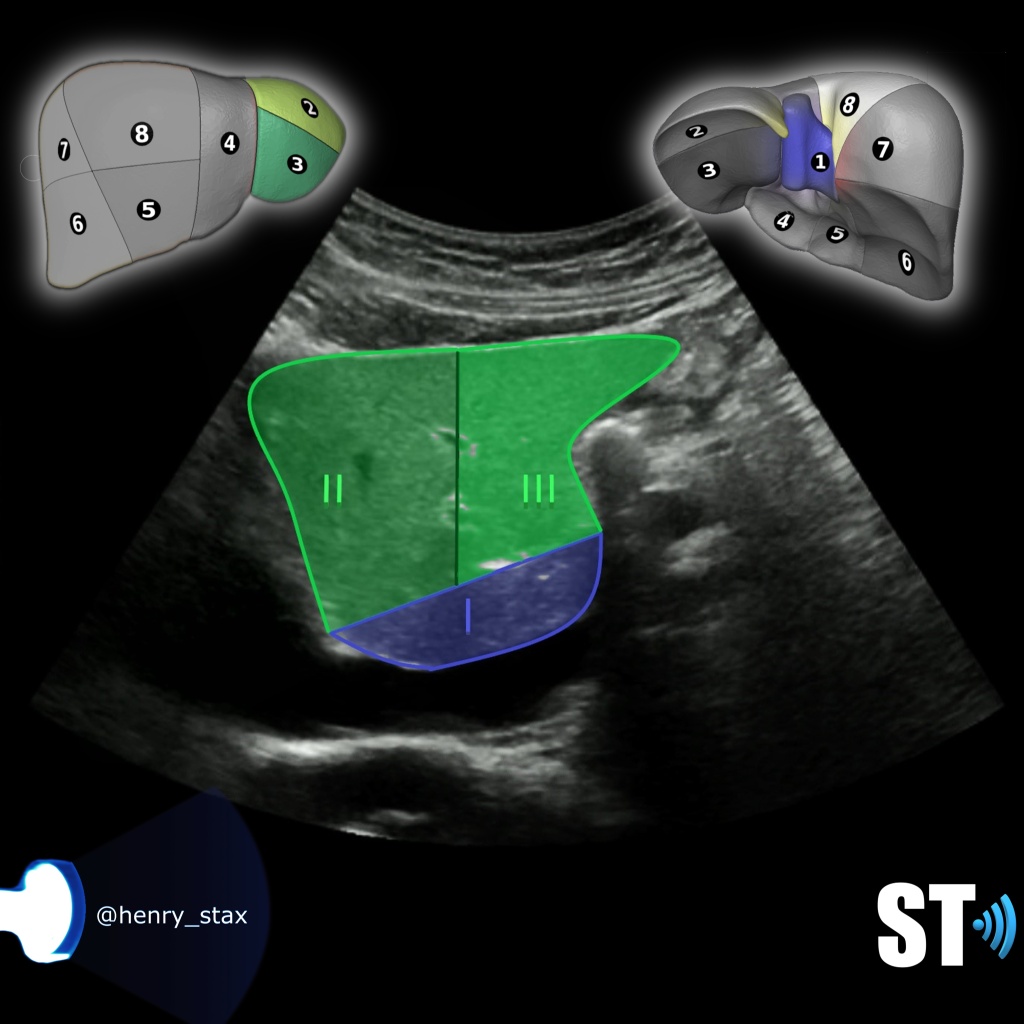

Caudate lobe segment I

Segment I,II and III

Segment I is the caudate lobe.

Segment II and III is the superior and inferior lateral left lobe.